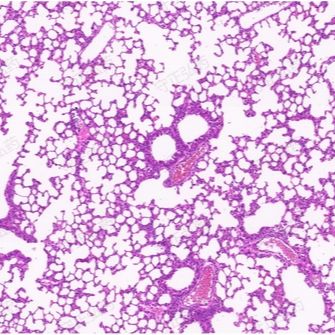

2) 肺组织病理学: 肺组织HE染色显示模型组肺泡融合扩张、肺小叶间质增生、炎细胞浸润、气道重塑等病理改变。